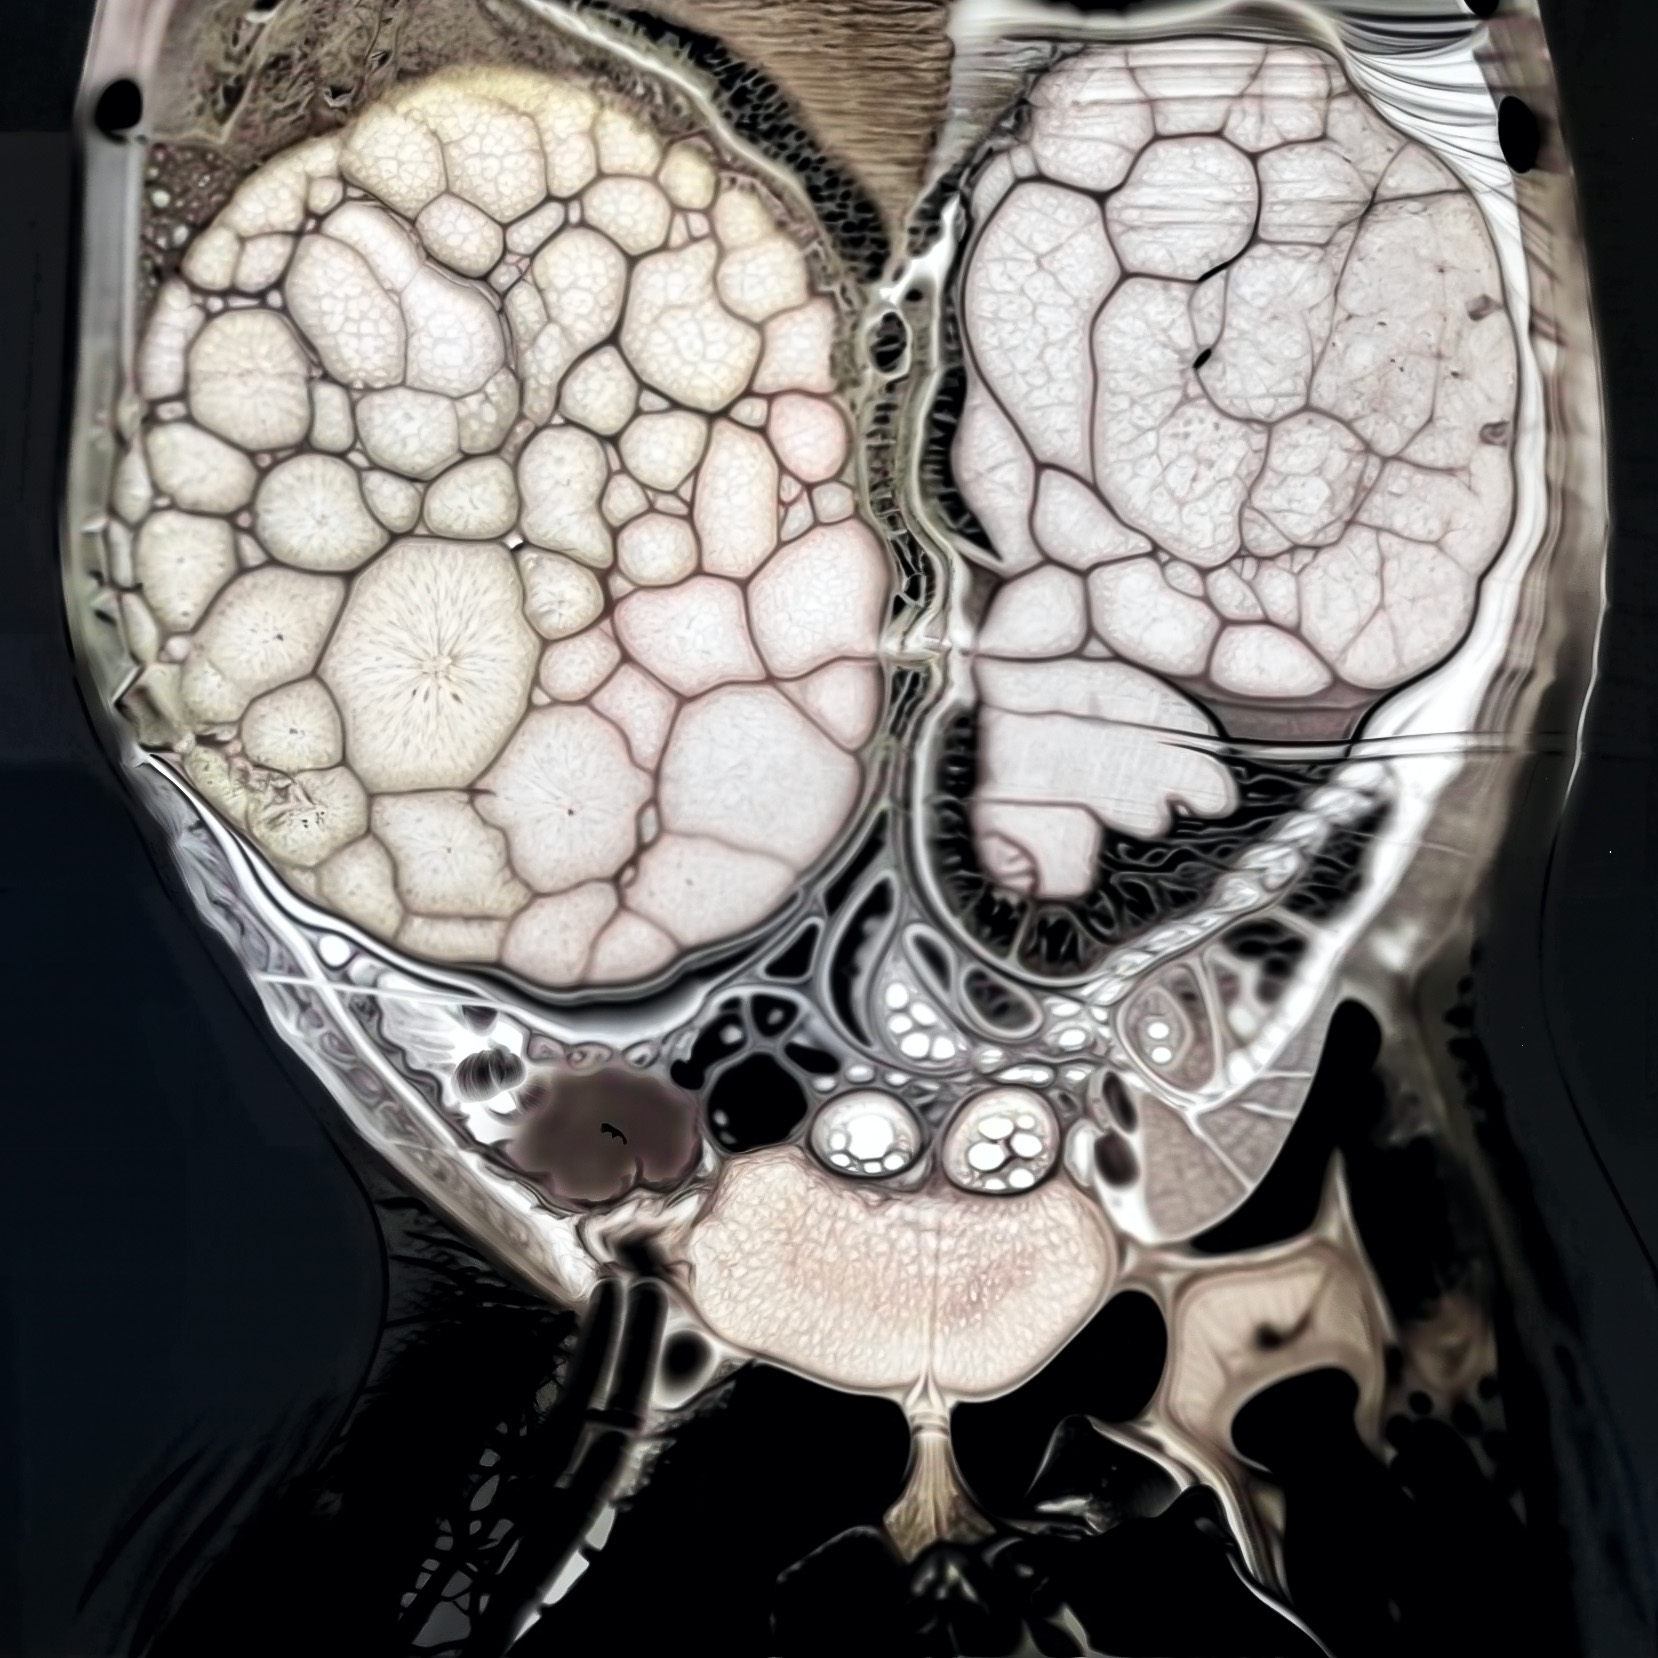

Iconography and Image Processing

BEFORE

AFTER

Faire glisser le slider